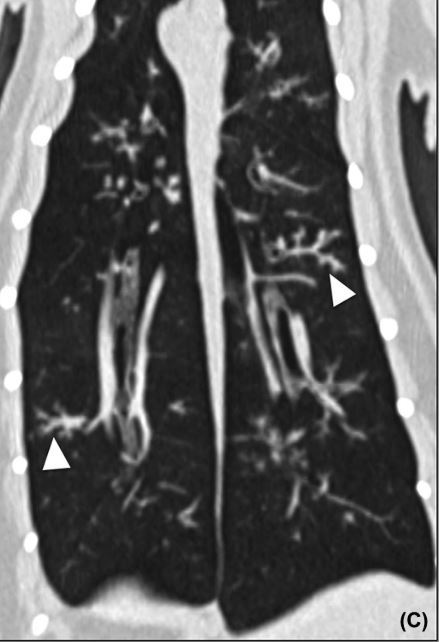

Hahn et al: CT and rad comparsion of asmatic cats: What does the “tree in bud” sign on CT represent?

A

Bronchiolar dilation with bronchiolar plugging by mucus, pus or fluid.

Usually associated with Bronchial disease

IT is non-enhancing

Hahn et al: CT and rad comparsion of asmatic cats: What is a mosaic pattern on CT and what does it mean?

A mosaic pattern is a patch work of hyper and hypoattenuation throughout the lungs.

This can mean two things:

1. Vascular disease causing shunting away from the affect area

2. Air trapping caused by bronchial disease or focal pulmonary emphysema.

1. Pulmonary emphysema is a permanent elargement of the air spaces caused by destruction of the walls of the air spaces. - On CT it shows loss of normal tissue

Only way to differentiate this is using expiratory series which if bronchial disease you will see the mosaic pattern more but if vascular then it will stay the same.

Hahn et al: CT and rad comparsion of asmatic cats: What lungs were most affected on both modalities?

Right cranial and right caudal

Hahn et al: CT and rad comparsion of asmatic cats: Which modality found the most lesions?

CT and some were asymptomatic